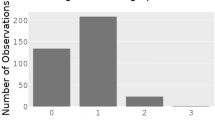

All results are presented in Table 2. ChatGPT/GPT-4 responses are available in detail in supplement S1. In all cases, all models advised contacting medical professionals. Calling EMS was advised in 94 cases (71.2%). Considering the six iterative presentations, ChatGPT/GPT-4 correctly identified 12 of 22 scenarios (54.5%) as emergencies of high urgency with the correct activation of the emergency response chain.

In case 17, the medical staff assessed the patient before contacting the AI. ChatGPT/GPT-4 ignored this in all six iterations and advised the emergency call. The cases with poor activation of the EMS were non-haemorrhagic shock, septic shock, supraventricular tachycardia, myocarditis, and pulmonary embolism.

Valid advice to first aiders was correct in 83 of 132 cases (62.9%) and considering the iterative approach in 10 of 22 scenarios (45.5%). The worst performance in advice could be detected in choking (ChatGPT/GPT-4 advises infant treatments, the Heimlich manoeuvre only once), opioid intoxication, Duchenne muscular dystrophy, haemorrhagic shock (advising a torniquet), supraventricular tachycardia (advising carotid pressure), and pericardial tamponade. In case 2 (airway swelling in anaphylaxis), ChatGPT-GPT-4 decided twice for hemodynamic anaphylactic shock treatment (lay down, legs raised) instead of respiratory treatment (elevated positioning).

The correct diagnosis was made in 124 of 132 cases (93.94%). The binomial test revealed that the observed proportion of correct diagnoses was not statistically lower than 95% considering all scenarios and iterations together (one-tailed p = 0.49). In three of 22 scenarios (13.6%), the diagnoses could not be made consistently. These were septic shock, pulmonary embolism, and pericardial tamponade. All other scenarios were identified correctly.

For the six other variables (CALL, ADVICE, DIAGNOSIS, ALTERNATIVE DIAGNOSIS, DISCLAIMER, PATIENT SAFETY), the observed proportion of correctly classified answers was significantly lower than 95% (one-tailed p < 0.05) throughout all cases and iterations. Only the variable ALS ADVICE did not show an observed proportion of correct answers lower than 95% (one-tailed p = 0.49).